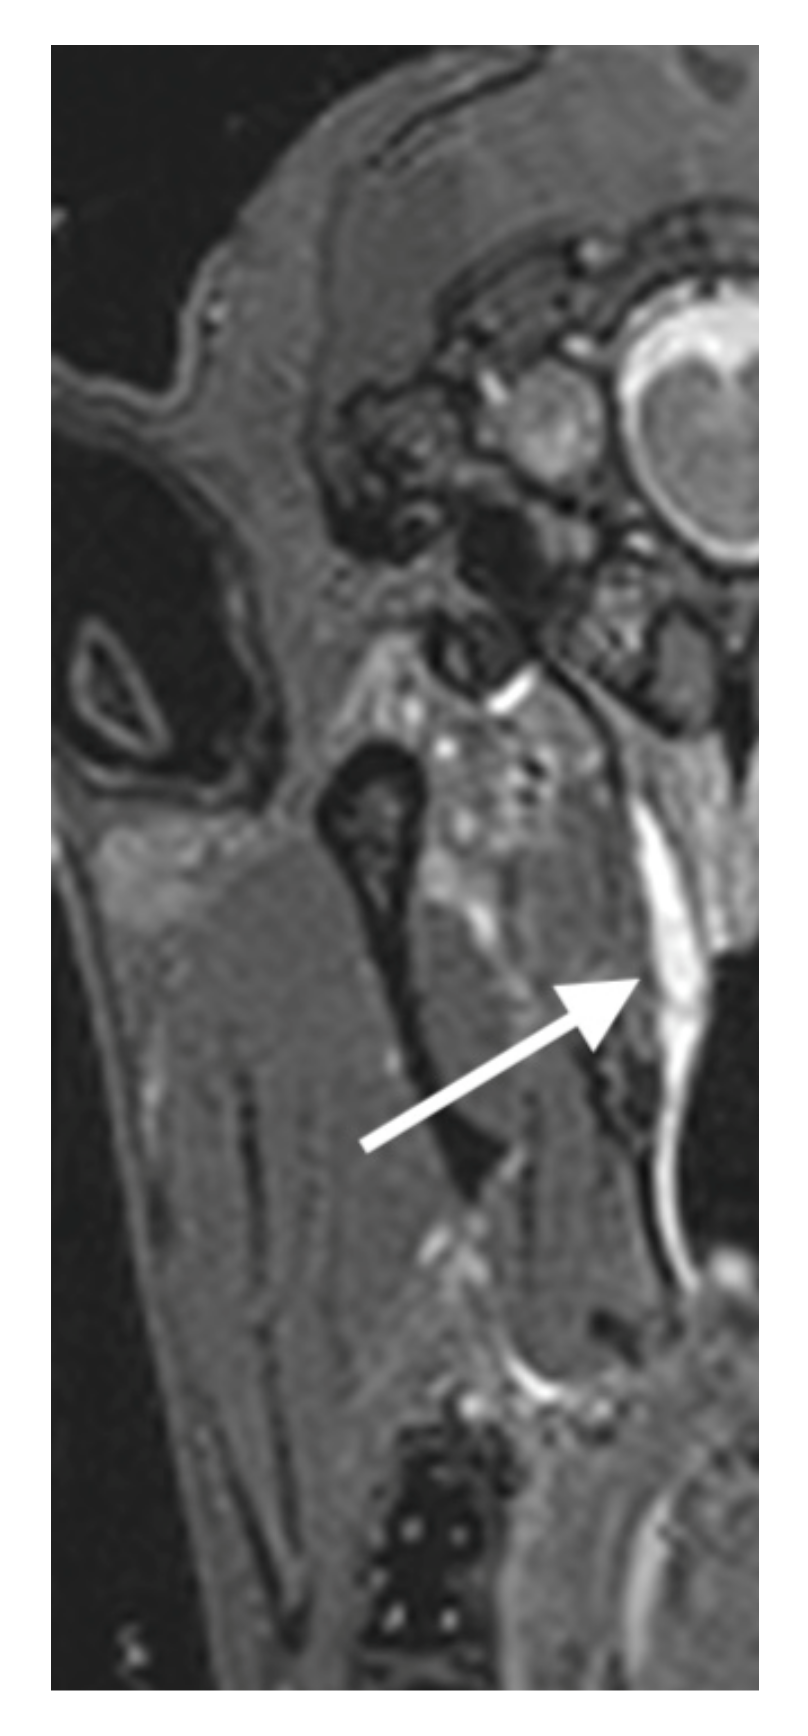

3.2.4. Imaging